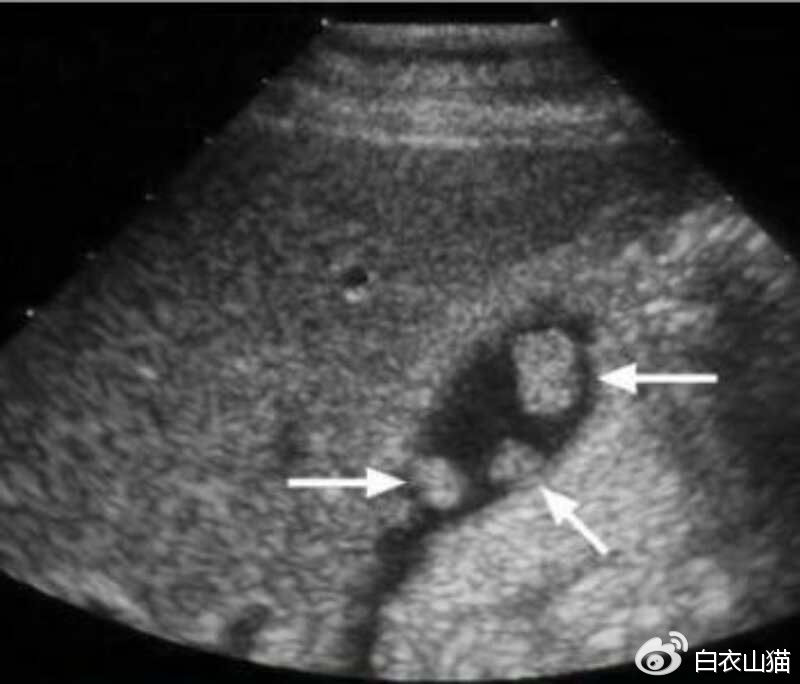

箭头所指就是胆囊息肉

息肉的B超表现有: 胆囊壁有强或稍强回声光团,其后无声影, 声像具体表现不会随着患者体位的改变 而发生移动现象。

B超检查中最重要的依据是息肉大小。

胆囊息肉的最重要检查,也是首选的检查:腹部B超。B超对人无害,又便宜。